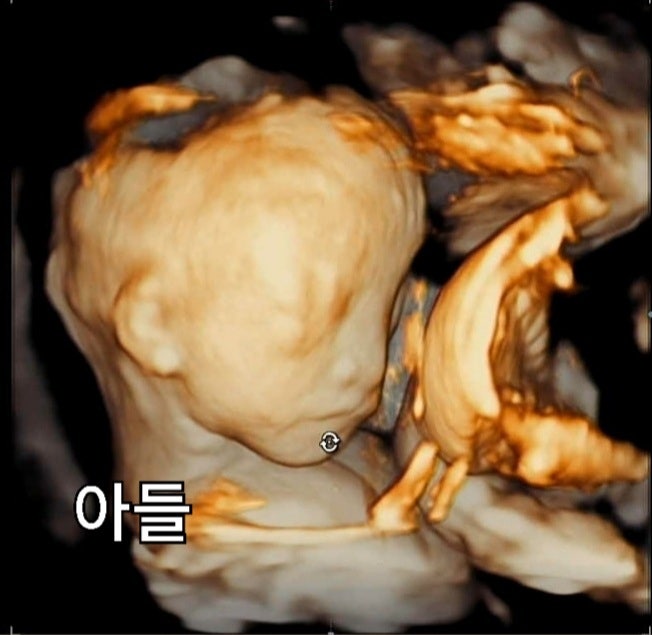

[임신일기]22주 4일차 입체초음파를 보다

3주만에 정기외래검진을 가는 날. 별다른 이유도 없고 단순 검진이라 그냥 아무 생각없이 갔는데, 입체초음...